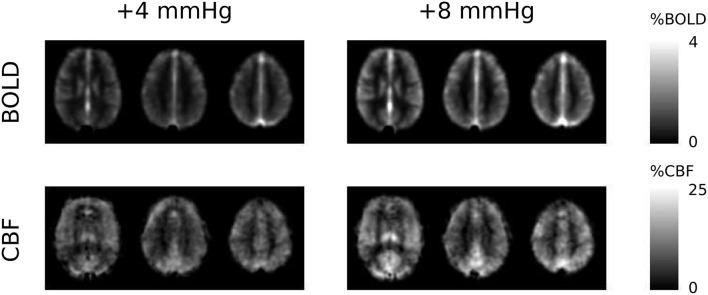

Calibrated BOLD is a promising technique that overcomes the sensitivity of conventional fMRI to the cerebrovascular state; measuring either the basal level, or the task-induced response of cerebral metabolic rate of oxygen consumption (CMRO). The calibrated BOLD method is susceptible to errors in the measurement of the calibration parameter , the theoretical BOLD signal change that would occur if all deoxygenated hemoglobin were removed. The original and most popular method for measuring uses hypercapnia (an increase in arterial CO), making the assumption that it does not affect CMRO. This assumption has since been challenged and recent studies have used a corrective term, based on literature values of a reduction in basal CMRO with hypercapnia. This is not ideal, as this value may vary across subjects and regions of the brain, and will depend on the level of hypercapnia achieved. Here we propose a new approach, using a graded hypercapnia design and the assumption that CMRO changes linearly with hypercapnia level, such that we can measure without assuming prior knowledge of the scale of CMRO change. Through use of a graded hypercapnia gas challenge, we are able to remove the bias caused by a reduction in basal CMRO during hypercapnia, whilst simultaneously calculating the dose-wise CMRO change with hypercapnia. When compared with assuming no change in CMRO, this approach resulted in significantly lower -values in both visual and motor cortices, arising from significant dose-dependent hypercapnia reductions in basal CMRO of 1.5 ± 0.6%/mmHg (visual) and 1.8 ± 0.7%/mmHg (motor), where mmHg is the unit change in end-tidal CO level. Variability in the basal CMRO response to hypercapnia, due to experimental differences and inter-subject variability, is accounted for in this approach, unlike previous correction approaches, which use literature values. By incorporating measurement of, and correction for, the reduction in basal CMRO during hypercapnia in the measurement of -values, application of our approach will correct for an overestimation in both CMRO task-response values and absolute CMRO.